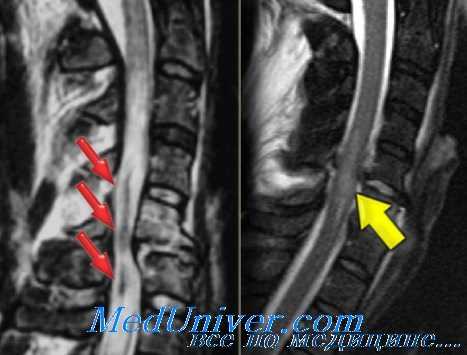

- выпадение межпозвонковой грыжи, ее окостенение или секвестрирование вследствие дископатии;

- переднее смещение позвонка (спондилолистез) вследствие анатомического дефекта дуги позвонка;

Зачастую на формирование стеноза позвоночного канала оказывают влияние как врожденные, так и приобретенные факторы. Страдают стенозом преимущественно пожилые люди, так как у них имеют место возрастные дегенеративные заболевания позвоночника. Частота заболевания резко возрастает у людей старше 50 лет и в данной возрастной группе составляет от 1.8 до 8%. [2] Наиболее часто встречающийся приобретённый стеноз позвоночного канала — это последняя стадия остеохондроза позвоночника, когда разрастается костная ткань тел позвонков и остеофитов.